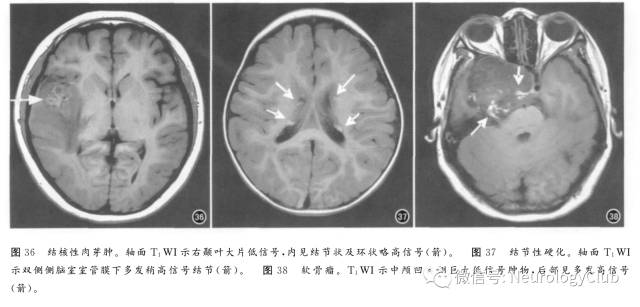

3. 结核性肉芽肿

也可引起短T1效应,可能与病变内巨噬细胞吞噬脂质有关。颅内结核好发于脑膜及脑实质(图36),尤以基底池、桥前池常见,呈结节状或斑片状轻度T1WI高信号,增强扫描明显强化,同时见到脑膜增厚及脑外结核有助于诊断。

4. 钙化

通常为T1WI与T2WI均呈低信号,但抗磁性钙盐加上其他顺磁性物质如铁和锰,也可导致T1缩短。甲状旁腺功能低下和亢进、甲状腺功能低下、线粒体脑病、Fahr病、CO中毒及特发性钙化是颅内钙化的常见原因,结节性硬化(图37)、软骨瘤(图38)也可见钙化及T1WI高信号。